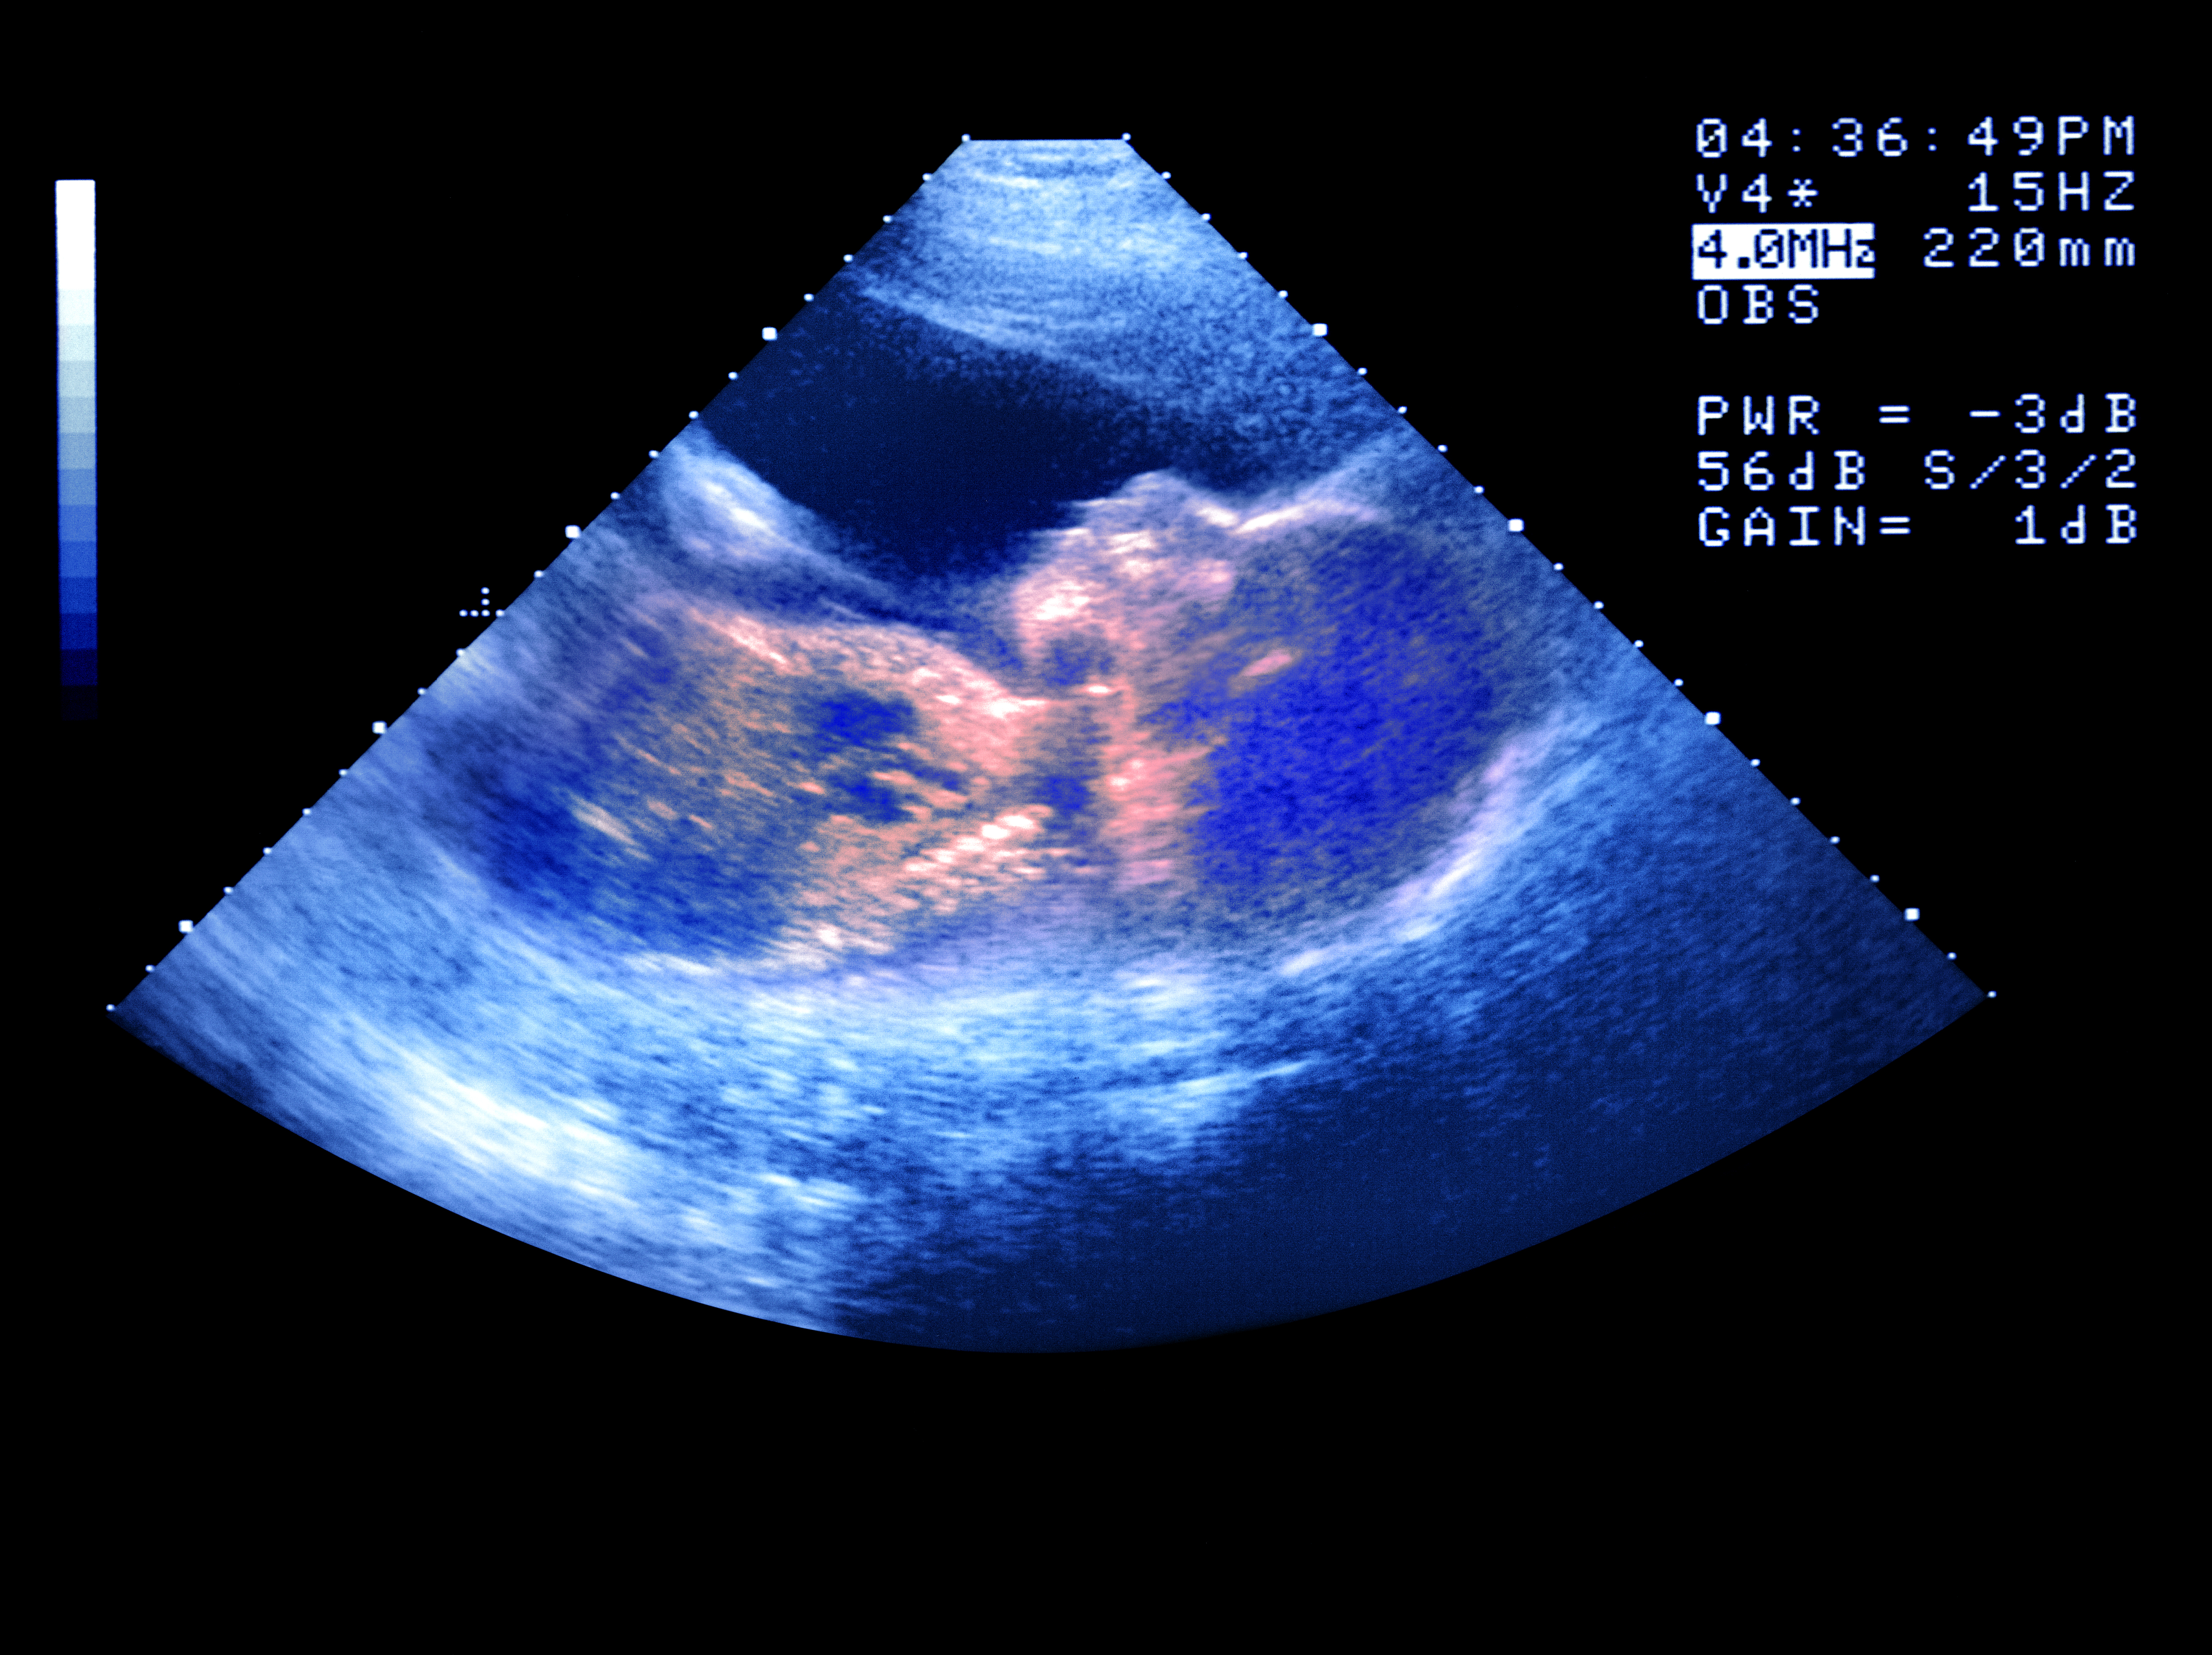

But a routine ultrasound scan at seven months picks up that Hess’s baby has an unusually protruding tongue. Her pregnancy has entered “complication mode”. Only after an MRI scan and rounds of testing does suspicion curdle into a diagnosis: a rare genetic condition called Beckwith-Wiedemann syndrome. “Don’t Google it,” the doctor warns. As if any millennial could resist.

Perinatal technologies, which parse what’s normal, have accompanied us from the start of human reproduction, whether sticks marked with 28 notches to count down our menstrual cycles or the Sims speculum, to lesser-known histories Hess includes with care and fascinating detail in Second Life, such as the first baby monitor from 1938, the 1950s advent of prenatal ultrasound that used “a naval tool for inspecting metal ships”, sex diagnosis and gender reveals, smart breast pumps, pulse oximeter booties, and cribs that shush, rock and watch over the little one so parents don’t have to.